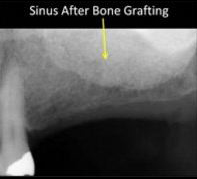

The above X-rays show the expanded sinus before and after bone grafting

Fortunately, Dr. Caldwell, Dr. Dimmitt, and other surgeons who have received specialized training in sinus surgery are now able to use predictable surgical techniques that actually “fill the base of the maxillary sinus” with a foundation of stable bone that is able to carry the “stress load” of implant supported bridgework. The statistical success rates for these procedures are excellent and these breakthroughs have provided a means of “reclaiming” this important portion of the mouth, allowing implants as long as 12 to 15mm to be placed in regions where, seven months before, the patient had less than 3 to 5mm of bony support.

Two surgical techniques are utilized to place bone in these deficient regions. The first technique is called a “Sinus Lift” and it involves the passage of bone through the hole that is prepared for the implant placement. This technique is utilized when small volumes of additional support are needed for implant success. The second technique, called a “Lateral Window Sinus Augmentation” involves access to the sinus through a “window in the side of the sinus” that is used for larger graft procedures. Both techniques allow the surgeon to “elevate the sinus lining membrane” away from the remaining bone, creating a “space” that is then filled with bone graft materials. This approach re-establishes a vertical bony foundation that is capable of carrying the load of implants after six to eight months of graft maturation. Implants that are placed in large sinus graft regions are often allowed to integrate for longer periods of time than routine implants, allowing the newly generated bone time to strengthen. Over-all, this technique has provided fixed implant supported bridges or implant retained dentures to be used in a large group of patients who were previously condemned to removable appliances.